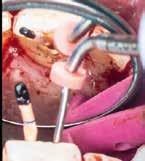

gyökércsatornában lévő pulpát is részlegesen eltávolítottuk. A sebészi feltáráshoz szükséges metszést a frenulum mellől indítottuk, majd intrasulcularisan, papillakímélő módon a szemfogig vezettük. A lebeny felemelését követően a csontos falú üregből a granulációs szövetet egy éles exkavátor segítségével eltávolítottuk.

1. a–c ábra: Kiindulási CBCT-felvétel. Az axiális síkú metszeten jól látható a gyökér falának perforációja (a); Koronális irányú metszet (b), Saggitális irányú metszet

9. a–b ábra: A műtét előtt (a) és a lebeny felemelését követően látható állapot (b). – 10. a–d ábra: A granulációs szövet eltávolítása.